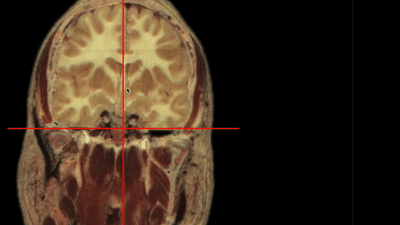

nv.get_volume_data ( x1, x2, y1, y2, z1, z2 )

maybe?

endless processing possibilities :)

nv.set_volume_data ( x1, x2, y1, y2, z1, z2, new data )

nv.set_label_data ( x1, x2, y1, y2, z1, z2, new data )

nv.get_label_data ( x1, x2, y1, y2, z1, z2 )

ROI Selection

Shruti Varade

all different!

soon in Boostlet.js!